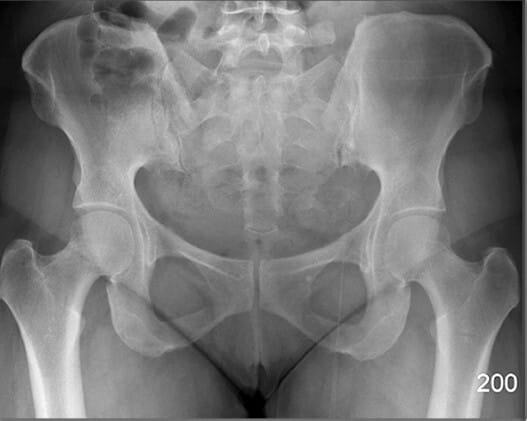

Bony Structures (AP View)

장골 (Ileum)

| 장골 (Ileum) |

| ✅ 골반의 상부를 구성하는 큰 뼈로, 장골능(iliac crest)과 전상장골극(ASIS) 등을 포함합니다. |

| 🔴 AP view에서는 넓은 곡선형 음영으로 관찰되며, 골반 골절 여부 평가에 중요합니다. |

장골능 (Iliac Crest)

| 장골능 (Iliac Crest) |

| ✅ 골반의 가장 상부 경계로, AP pelvis 영상에서 양측 상단에 대칭적으로 보입니다. |

| 🔴 곡선을 이루며, 체위 기준점으로도 활용됩니다. |

전상장골극 (ASIS, Anterior Superior Iliac Spine)

| 전상장골극 (ASIS, Anterior Superior Iliac Spine) |

| ✅ 장골의 앞쪽 윗부분에 돌출된 뼈로, AP view에서 골반의 가장 상전방에 대칭적으로 위치합니다. |

| 🔴 표면해부학에서 중요한 구조로 , 골반의 변위를 대략적으로 파악할 수 있습니다. |